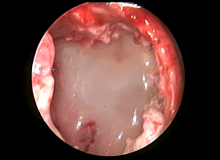

Postesophagectomy Drainage of Subcarinal Collection via Mediastinoscopy [1]

This video demonstrates the drainage of a subcarinal collection via mediastinoscopy in a patient who had recently undergone esophagectomy. The chyle leak was localized over the gastric conduit and unsuccessfully drained percutaneously. However, computed tomography imaging showed a 4.9 mm margin inferior to the carina whereby drainage could be accomplished via mediastinoscopy.